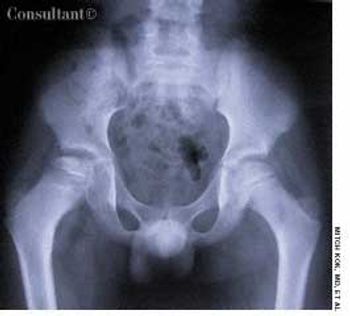

A roentgenogram of the kidneys, ureter, and bladder of a 58-year-old man shows bilateral stones in the renal pelvis and the renal calyces. The patient had a history of recurrent urinary tract infections caused by Proteus mirabilis. A ureteral catheter (pigtail) had been placed in the pelvis of the left kidney to facilitate drainage.